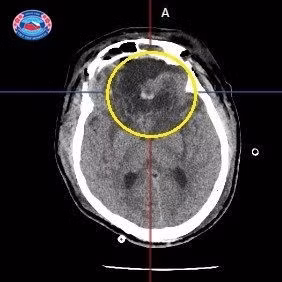

Rachael lần đầu tiên bị ốm khi mới 24 giờ tuổi. Kết quả chụp cắt lớp cho thấy cô bị bệnh u xơ toàn thân bẩm sinh dạng nặng nhất. Rối loạn hiếm gặp khiến các khối u lành tính phát triển ở da, cơ, xương và các cơ quan.